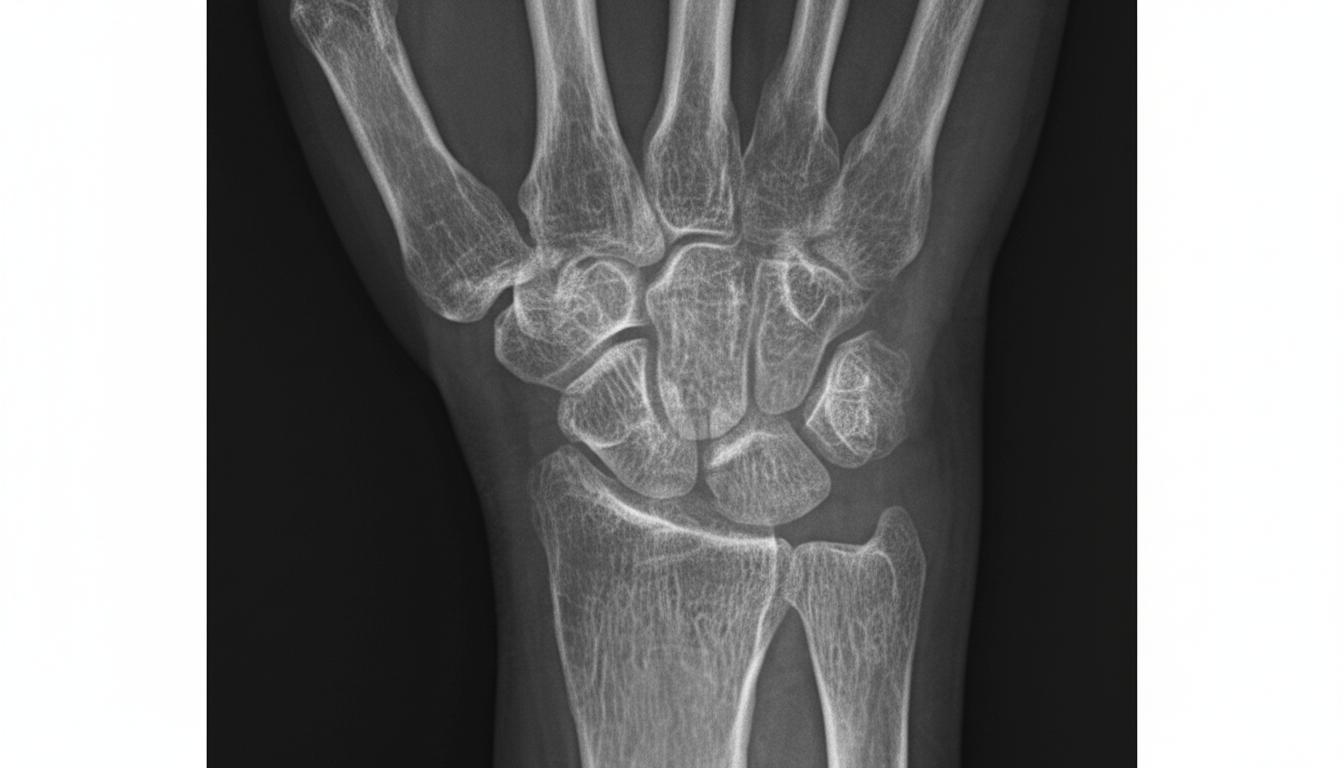

What is the estimated age from the given X-ray?

Explanation: ***More than 16 years*** - **Complete fusion of epiphyses** at the distal radius and ulna indicates skeletal maturity beyond 16 years of age. - The **absence of visible epiphyseal lines** and full ossification of carpal bones confirms age estimation above 16 years. *More than 12 years* - While **epiphyseal fusion begins** around 12-14 years, complete fusion occurs later, making this age estimate insufficient. - **Partial fusion** would still be visible at 12-14 years, not the complete ossification seen in mature bones. *Less than 16 years* - **Unfused epiphyseal plates** would be clearly visible in individuals under 16 years of age. - **Incomplete carpal ossification** and visible growth plates would indicate ongoing skeletal development. *Less than 12 years* - **Multiple unfused epiphyses** and **incomplete carpal bone development** would be evident at this age. - The **pisiform bone** typically appears around 12 years, and its presence with fused epiphyses rules out this age range.